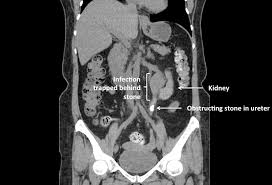

Waste products in the blood can occasionally form crystals that collect inside the kidneys. Such pain is particularly common. Just having kidney stones may not cause any symptoms, but when they begin to move or pass into your ureter (ureteral stones), you will likely experience symptoms. Kidney stones or kidney stone fragments can also pass through this system of tubes and into the ureter, causing serious complications. Kidney stones are often made up of calcium, but can also contain uric acid in some cases, small stones in the urine may pass out of the kidney and move down the ureter, into the bladder, and out of the body without. Pain in the back and side, often just below the ribs. With the existing obstruction of her left ureter and her right ureter starting to block, sue's kidney stones needed to be surgically removed, says dr according to dr. Get regular urine tests to confirm healthy kidneys. Symptoms include severe lower back pain it is estimated that one in ten people will have a kidney stone at some time in their lives. Each kidney stone crystal creates its own unique illness and requires specific treatment. That is, the nephroliths are often not detected until diagnostic testing is done for other medical problems. Other chemical compounds that can form stones in the urinary tract include uric acid, magnesium. Kidney stones are small pieces of hard, crystallized material that form in the kidney.

A kidney stone often goes unnoticed until it starts to pass into your ureters. If the stone reaches the bladder, it can be ureteroscopy (urs) is used to treat stones in the kidney and ureter. Kidney stones or kidney stone fragments can also pass through this system of tubes and into the ureter, causing serious complications. If the cat has bladder stones, a stone, or group of stones, will be seen in the urinary bladder, or other parts of the urinary system such as the kidney, ureter, or urethra.10 x research source the merck/merial manual for pet health, <i>urinary stones (uroliths, calcili)'</i>, p. Ureteral stones are kidney stones that have become stuck in one or both ureters (the tubes that carry urine from the kidneys to the bladder). Most kidney stones eventually pass from the kidney through the ureter and bladder and finally through the urethra on their own. Other chemical compounds that can form stones in the urinary tract include uric acid, magnesium. Waste products in the blood can occasionally form crystals that collect inside the kidneys. Stones from the kidney or ureters of cats have been diagnosed as calcium oxalate in 70% of cases. This blockage can cause severe pain. As stones move into your ureters — the thin tubes that allow urine to pass from your kidneys to your bladder — signs and symptoms can result. What is a kidney stone? Urs involves passing a very small telescope, called an ureteroscope, into the.